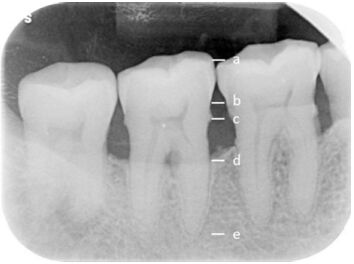

60.下列 X 光影像中,a 與 b 標示分別為何?

(A)a:顴突(zygomatic process),b:上顎竇(maxillary antrum)底部 (B)a:顴突(zygomatic process),b:齒槽嵴尖(alveolar crest) (C)a:上顎竇(maxillary antrum)底部,b:齒槽嵴尖(alveolar crest) (D)a:上顎竇(maxillary antrum)底部,b:顴突(zygomatic process)

68.附圖 X 光片中 47 近心側齒槽骨流失的比例,應如何計算? (a:近心邊緣嵴,b:牙骨質-牙釉質交界,c:牙骨質-牙釉質交界往牙根 2 mm 處,d:齒槽嵴尖,e:牙 根尖)

(A)(b 至 d 距離)÷(a 至 e 距離)× 100% (B)(b 至 d 距離)÷(b 至 e 距離)× 100% (C)(c 至 d 距離)÷(c 至 e 距離)× 100% (D)(c 至 d 距離)÷(b 至 e 距離)× 100%